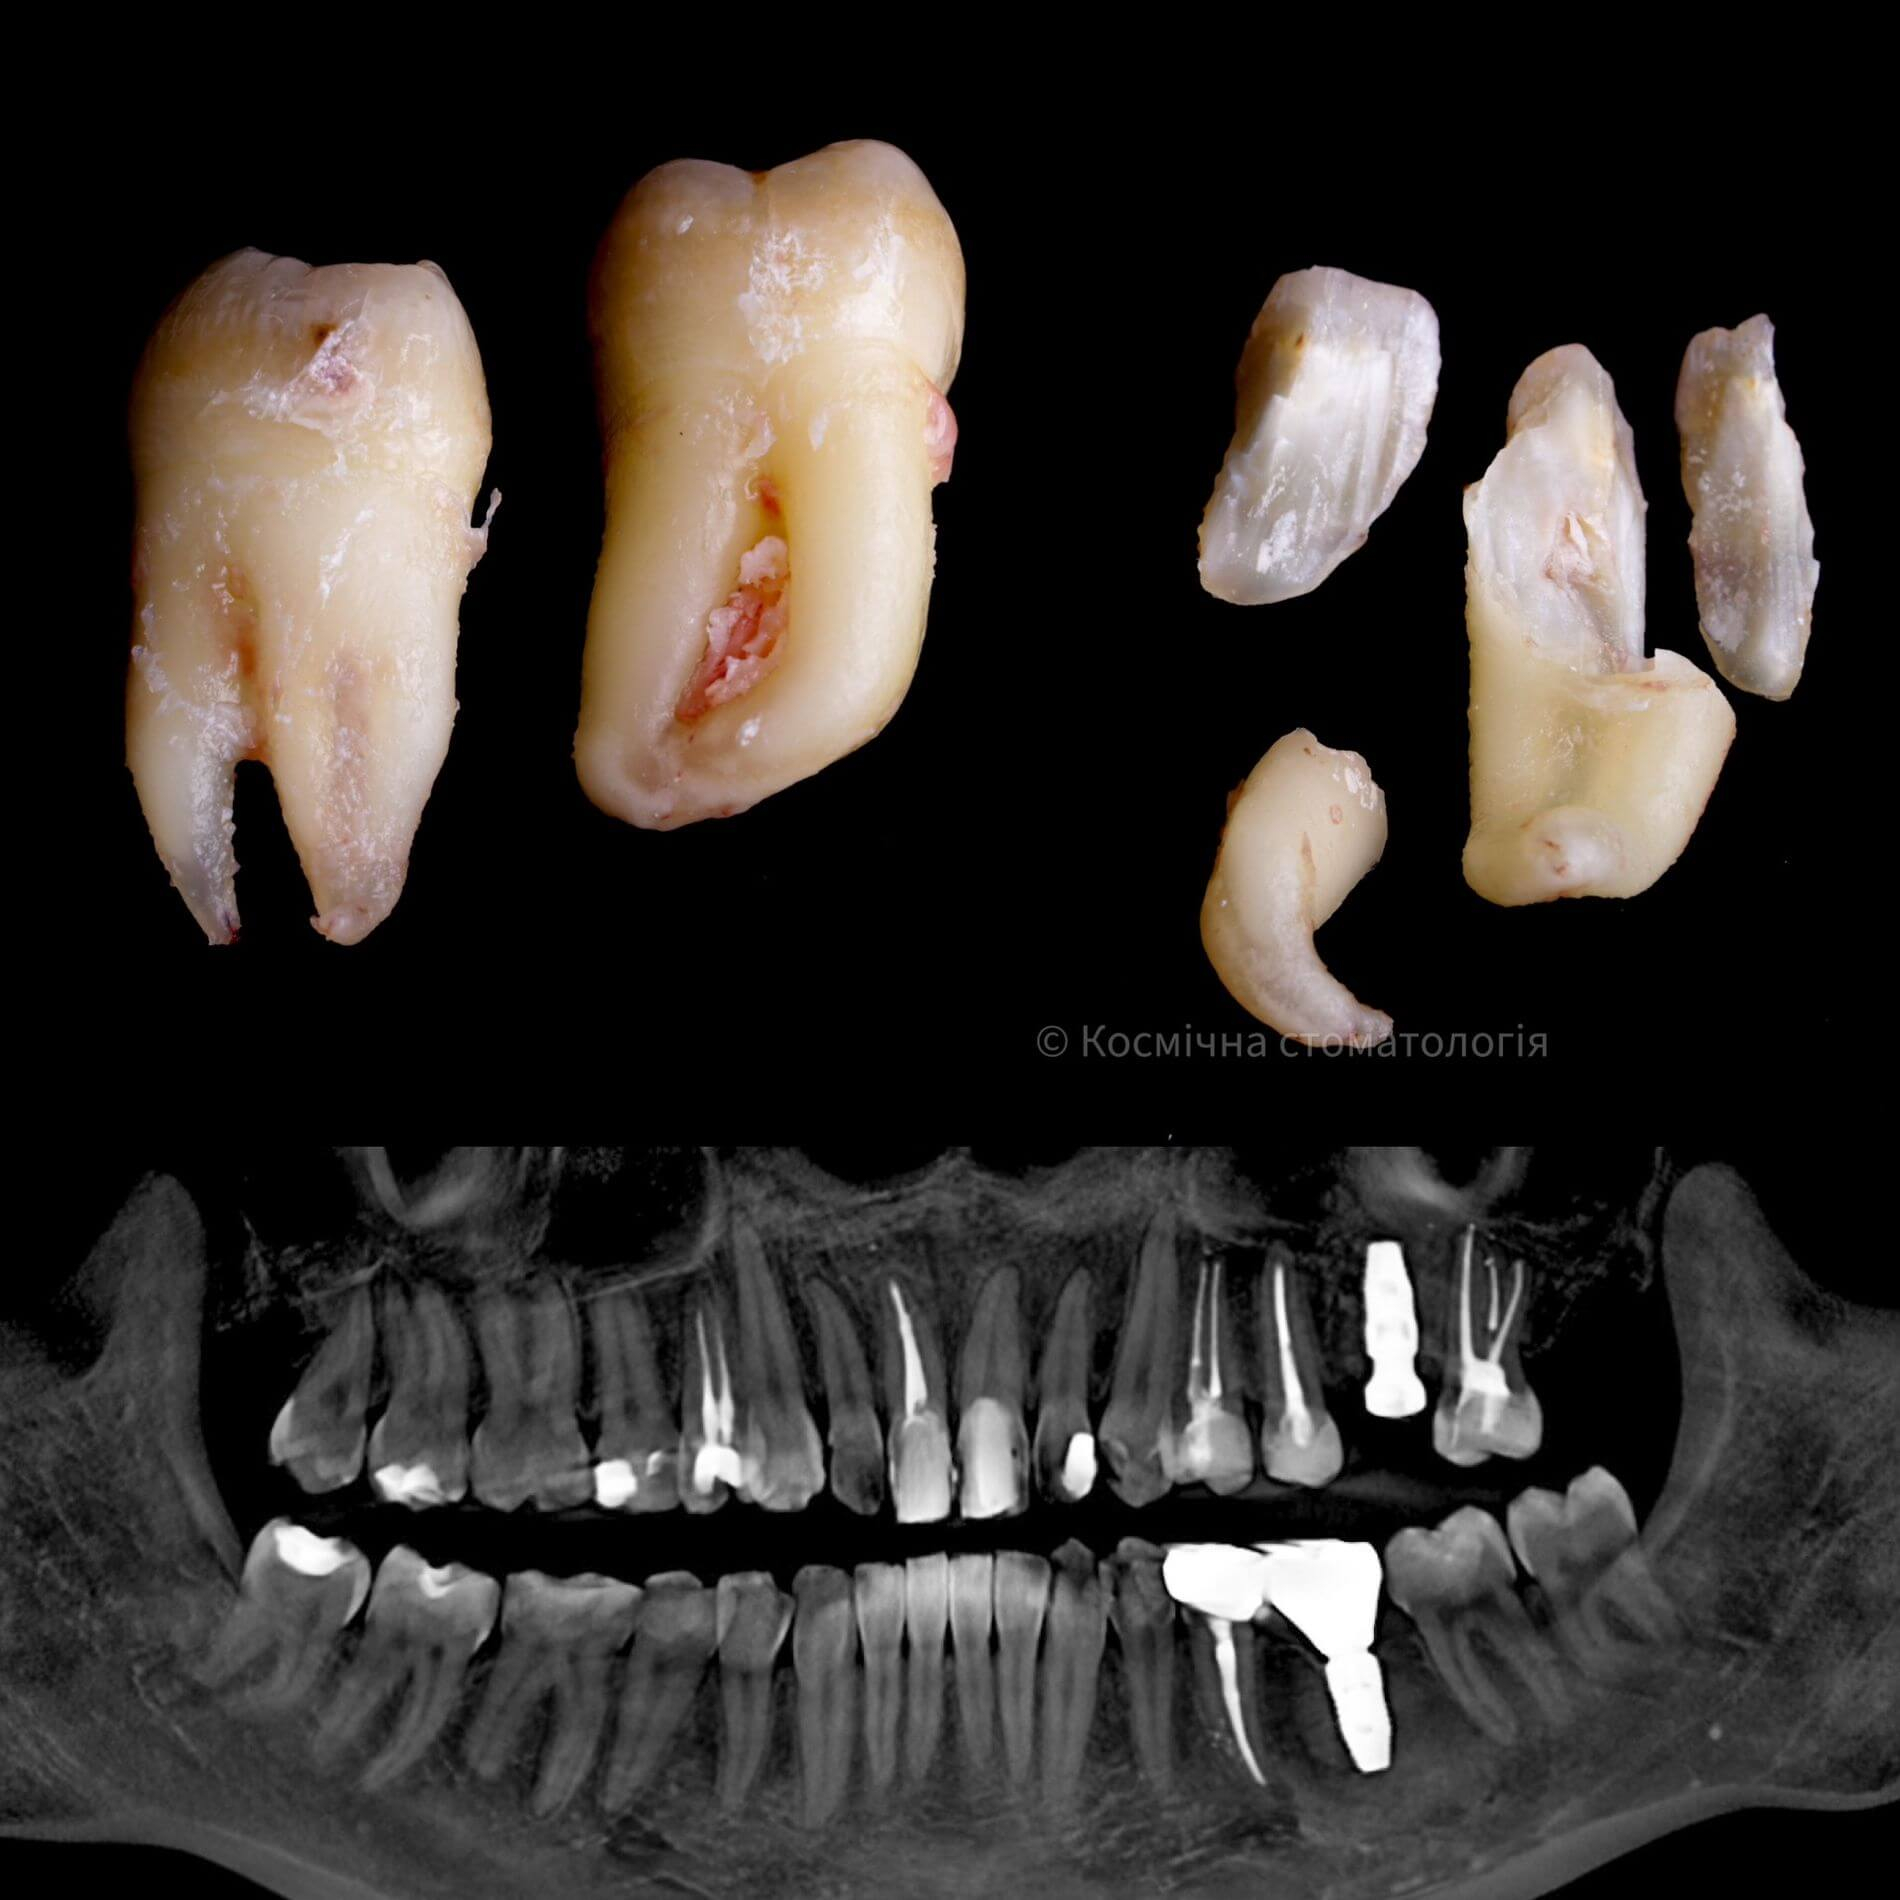

• Полное удаление зуба - если зуб полностью прорезался и имеет сросшиеся корни.

• Отдельное удаление коронки зуба и его корней - если зуб прорезан и корни растут по отдельности.

• Удаление зуба по схеме 1 или 2 с разрезом десен - если зуб прорезан частично.

• Разрез десен, освобождение зуба от близлежащей кости ультразвуком и удаление по схеме 1 или 2 - если зуб не прорезался, но беспокоит.

Галерея